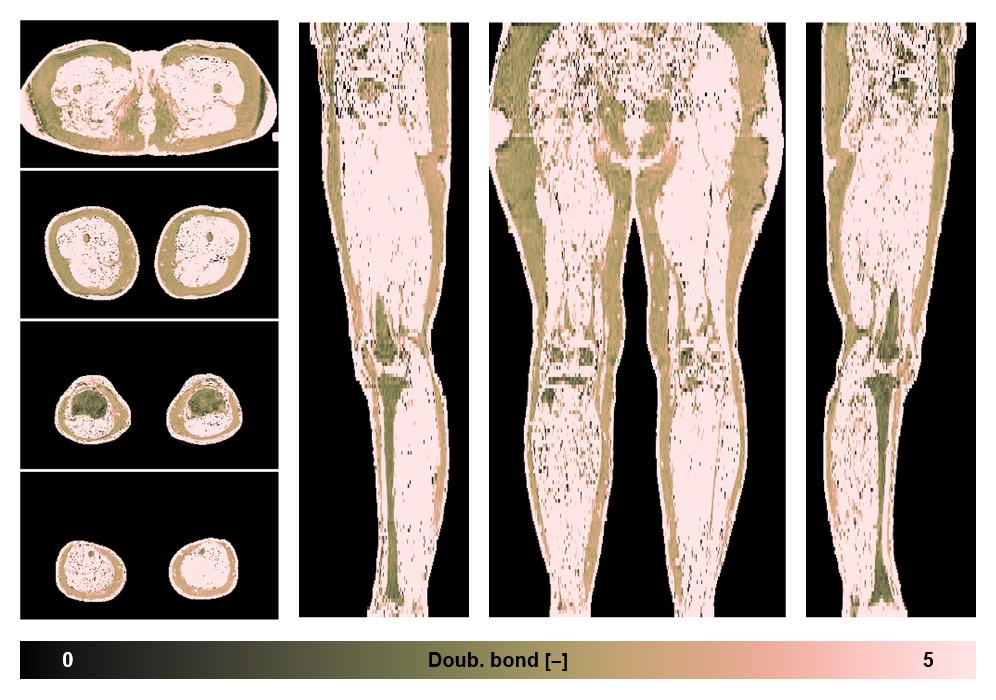

• Number of double bonds in subcutanious fat

Number of double bonds in subcutanious fat.